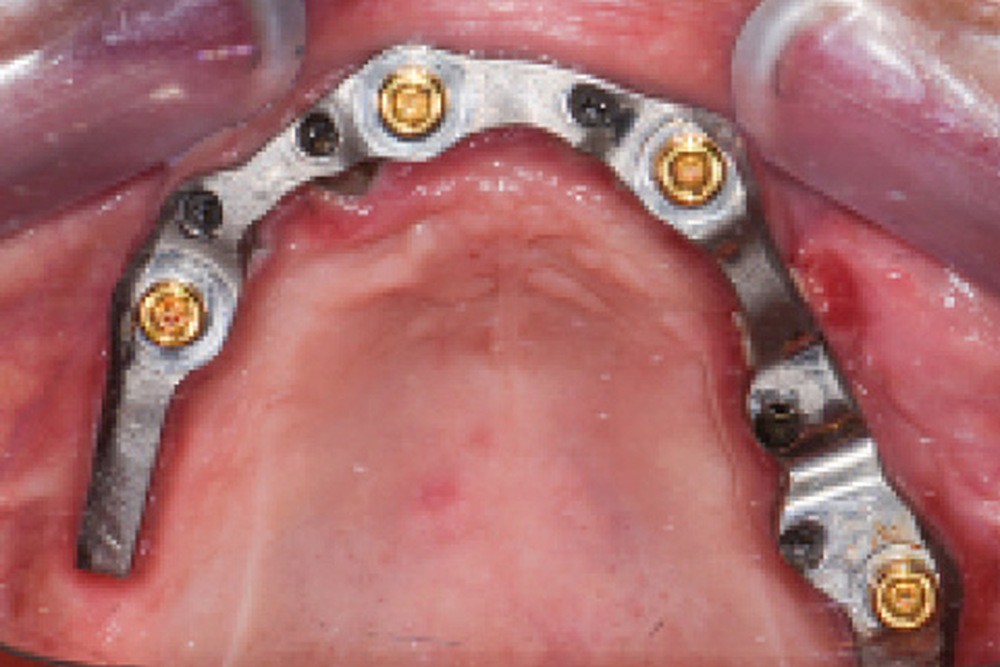

Une réhabilitation par PACSI maxillaire a été réalisée dix ans auparavant sur 5 implants en place de 13, 12, 21 et sur 24 et 26 (fig. 2a et b). Dans le cadre du plan de traitement initial, 6 implants avaient été indiqués. L’un d’entre eux, en position distale dans le secteur I, n’a jamais été ostéointégré. La patiente ne souhaitant plus de chirurgie, il avait donc été décidé de réaliser une prothèse sur 5 implants. La barre est directement connectée aux implants. À la mandibule, la patiente présente également une PACSI sur 2 implants associés à 2 piliers Locator®.

Lors de l’examen clinique, après dépose de la prothèse et dévissage de la barre, le constat est alarmant : présence de plaque abondante…